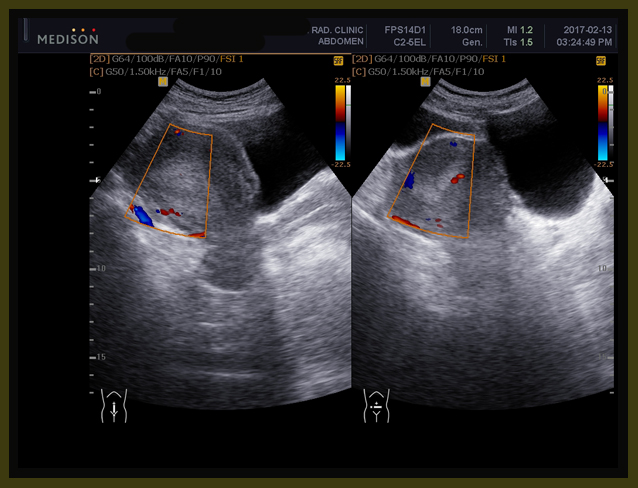

위에 보듯이 폐에 보이는 무수한 점들은 CT상에서는 더욱 선명하다. 다음에 PET에 나타나는 검은 점이나 CT상에서 동그란 솜 뭉쳐 놓은 것처럼 보이는 작은 원형의 점들이 모두 폐에 다발적으로 전이된 암을 표현한다.

1-10.jpg